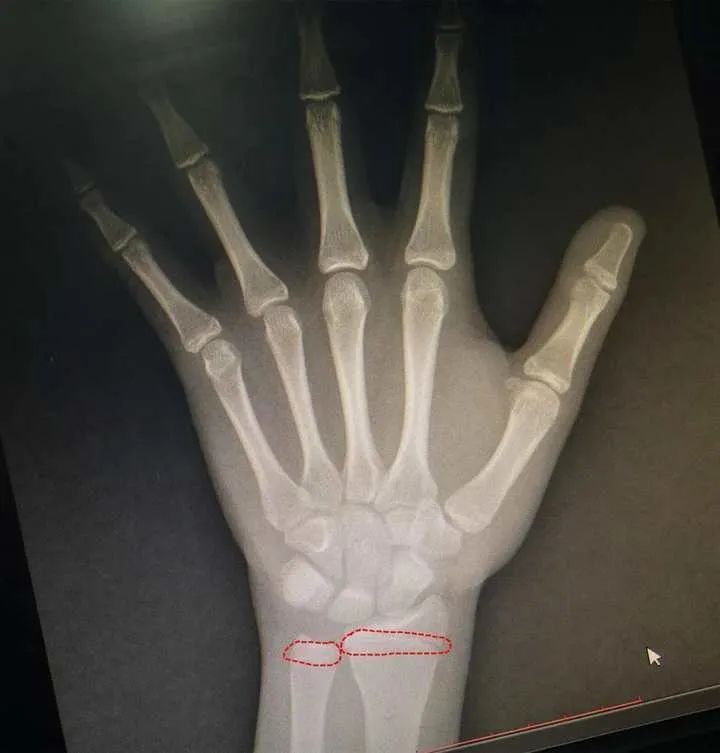

13岁小振的骨龄片

“也就是说,已经几乎没有长高的空间了!”树兰(杭州)医院儿科主任覃珍主任医师介绍,原本按照孩子父母的身高,小振的身高能长到172cm,但是肥胖导致他提早发育,提前透支了他的生长空间。